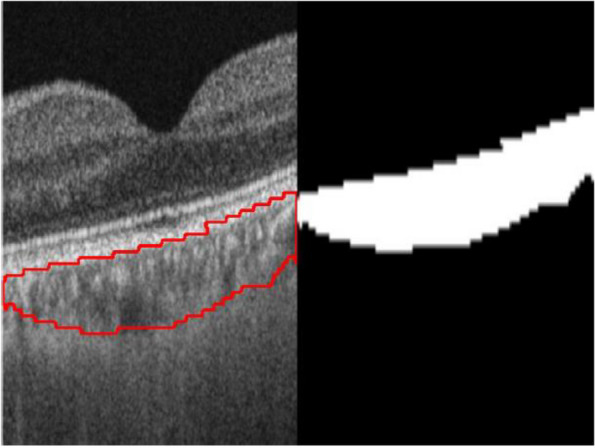

Methods: Subjects aged ≥ 16 years, with myopia of ≥ 0.50 diopters in both eyes, were recruited from the Prospective Myopia Cohort Study in Singapore (PROMYSE). OCT scans were acquired using Triton DRI-OCT and PLEX Elite 9000. OCT images were segmented both automatically with an established SA-Net architecture and manually using a standard technique with adjudication by two independent graders. SFCT was subsequently determined based on the segmentation. The Bland-Altman plot and intraclass correlation coefficient (ICC) were used to evaluate the agreement.

Results: A total of 229 subjects (456 eyes) with mean [± standard deviation (SD)] age of 34.1 (10.4) years were included. The overall SFCT (mean ± SD) based on manual segmentation was 216.9 ± 82.7 µm with Triton DRI-OCT and 239.3 ± 84.3 µm with PLEX Elite 9000. ICC values demonstrated excellent agreement between AI-automated and manual segmented SFCT measurements (PLEX Elite 9000: ICC = 0.937, 95% CI: 0.922 to 0.949, P < 0.001; Triton DRI-OCT: ICC = 0.887, 95% CI: 0.608 to 0.950, P < 0.001). For PLEX Elite 9000, manual segmented measurements were generally thicker when compared to AI-automated segmented measurements, with a fixed bias of 6.3 µm (95% CI: 3.8 to 8.9, P < 0.001) and proportional bias of 0.120 (P < 0.001). On the other hand, manual segmented measurements were comparatively thinner than AI-automated segmented measurements for Triton DRI-OCT, with a fixed bias of - 26.7 µm (95% CI: - 29.7 to - 23.7, P < 0.001) and proportional bias of - 0.090 (P < 0.001).

Conclusion: We observed an excellent agreement in choroidal segmentation measurements when comparing manual with AI-automated techniques, using images from two SS-OCT systems. Given its edge over manual segmentation, automated segmentation may potentially emerge as the primary method of choroidal thickness measurement in the future.